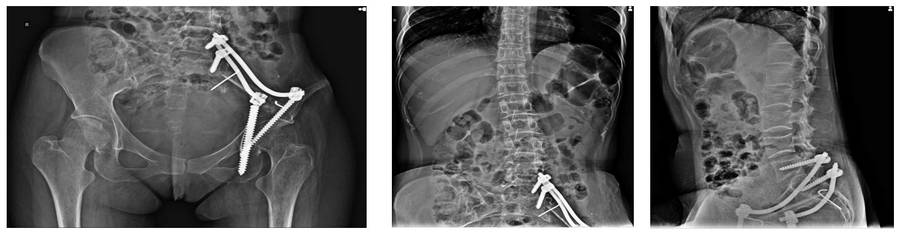

Before the surgery: The X-ray shows sacroiliac resection and reconstruction performed in the first surgery, as well as lumbar vertebral fractures and deformity.